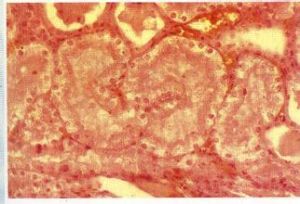

介紹是組織細胞最輕微的最易發生的一種細胞變性。說明其特點是變性的細胞腫大,在其胞漿內出現微細的淡紅色顆粒,核淡染。由於發生顆粒變性的實質器官如肝、腎、心外觀腫脹、混濁,呈土黃色,似沸水燙過一樣,故過去有混濁腫脹或濁腫之稱。